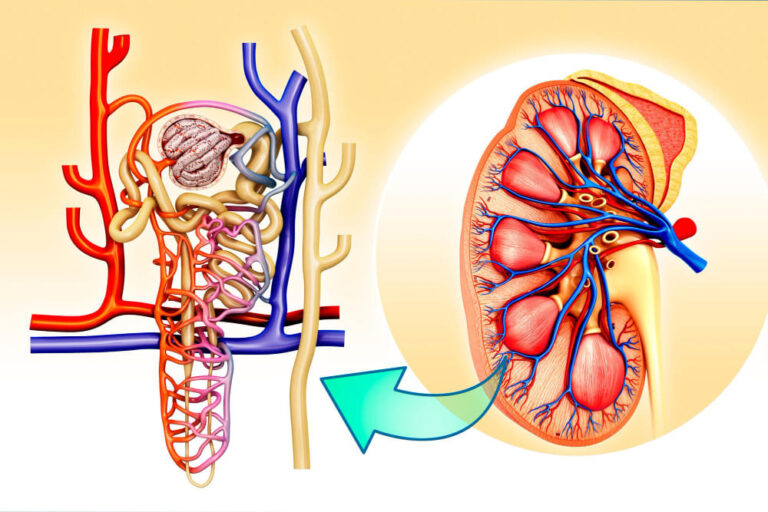

الكلى هي “فلتر” الجسم، ولكي تعمل بكفاءة، تحتاج إلى كمية كافية من الدم المحمل بالأكسجين. يصل هذا الدم عبر الشريان الكلوي. بمرور الوقت، وبسبب عوامل مثل التدخين، الكوليسترول، أو التقدم في العمر، قد تتراكم الدهون والترسبات على جدران هذا الشريان، مما يسبب ما يعرف بـ تصلب الشرايين.

عندما يحدث ضيق في الشريان الكلوي، يقل تدفق الدم للكلى. تترجم الكلى هذا النقص على أنه انخفاض في ضغط الجسم، فتقوم بإفراز هرمونات ترفع ضغط الدم بشكل جنوني لمحاولة تعويض النقص.

ضيق شرايين الكلى (Renal Artery Stenosis) يعني أن الأوعية الدموية المغذية للكلى أصبحت أضيق بسبب تراكم الدهون أو تصلب الشرايين.

هذا الضيق يقلل من تدفق الدم، فيحاول الجسم تعويض ذلك بزيادة ضغط الدم،